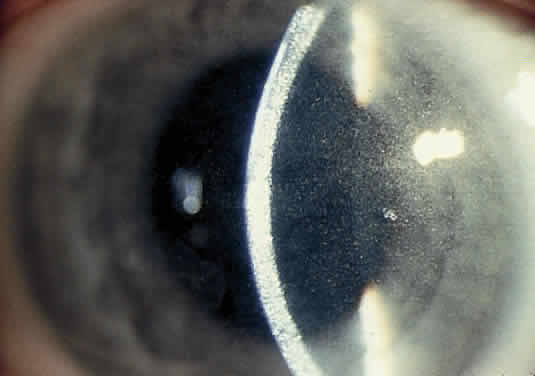

OCULAR FINDINGS. One of the few truly diagnostic and pathognomonic physical signs in clinical medicine is a Kayser-Fleischer corneal pigment ring found in patients with Wilson's disease (Fig. 5).This ring is recognized as a golden-brown, ruby-red, or green band of 1.0 to 3.0 mm, starting at the limbus but at the level of Descemet's membrane.53 The color of the ring is presumably caused by scattering and reflection of incident light and by photointerference effects created by the layers of copper granules. Such variables as size, shape, and unit density of the granules may account for the different appearances of the Kayser-Fleischer ring. The course of the Kayser-Fleischer ring has been well documented.54,55 The site of earliest pigment deposition is an arc in the superior periphery of the cornea from the 10- to 2-o'clock meridian. The arc spreads slowly toward the horizontal plane and gradually broadens. Later in the progression of the ring formation, a band appears inferiorly as a crescent stretching from the 5- to 7-o'clock positions. In time, the two arcs meet. With treatment, the sequence of events is reversed, and after the copper has reabsorbed, a pitted or beaten silver pattern may become apparent at the previous site of the ring. This is an indication that treatment has produced a negative copper balance.49 Decreased visual acuity is not a problem. Rarely, copper is deposited in the crystalline lens, giving an anterior subcapsular “sunflower” cataract.

Fig. 5. Wilson's disease. Kayser-Fleischer peripheral corneal ring. Copper pigment at level of Descemet's membrane.

PATHOLOGY. Electron microscopic, x-ray energy spectroscopic, and atomic absorption spectroscopic studies of the Kayser-Fleischer rings have revealed electron-dense granules rich in copper and sulfur in both the peripheral and the central region of the cornea, but more abundantly at the periphery. The association of copper with sulfur suggests that a sulfur-containing moiety functions in binding copper.59

MANAGEMENT. D-penicillamine (Cuprimine) is an extremely effective chelating agent because of its ability to mobilize copper from the tissues and increase its excretion in urine.52,60 Treatment of Wilson's disease with penicillamine is effective when started before there is active liver disease. After prolonged treatment with penicillamine, Kayser-Fleischer rings may fade, neurologic signs may clear, and liver function abnormalities may disappear. However, Kayser-Fleischer ring regression does not correlate with neuropsychiatric improvement.61 With D-penicillamine or after liver transplantation,62 Kayser-Fleischer rings disappear in reverse order to their formation. In most patients, the neurologic and hepatic lesions remit; hence the importance of recognizing the significant corneal pigment rings.